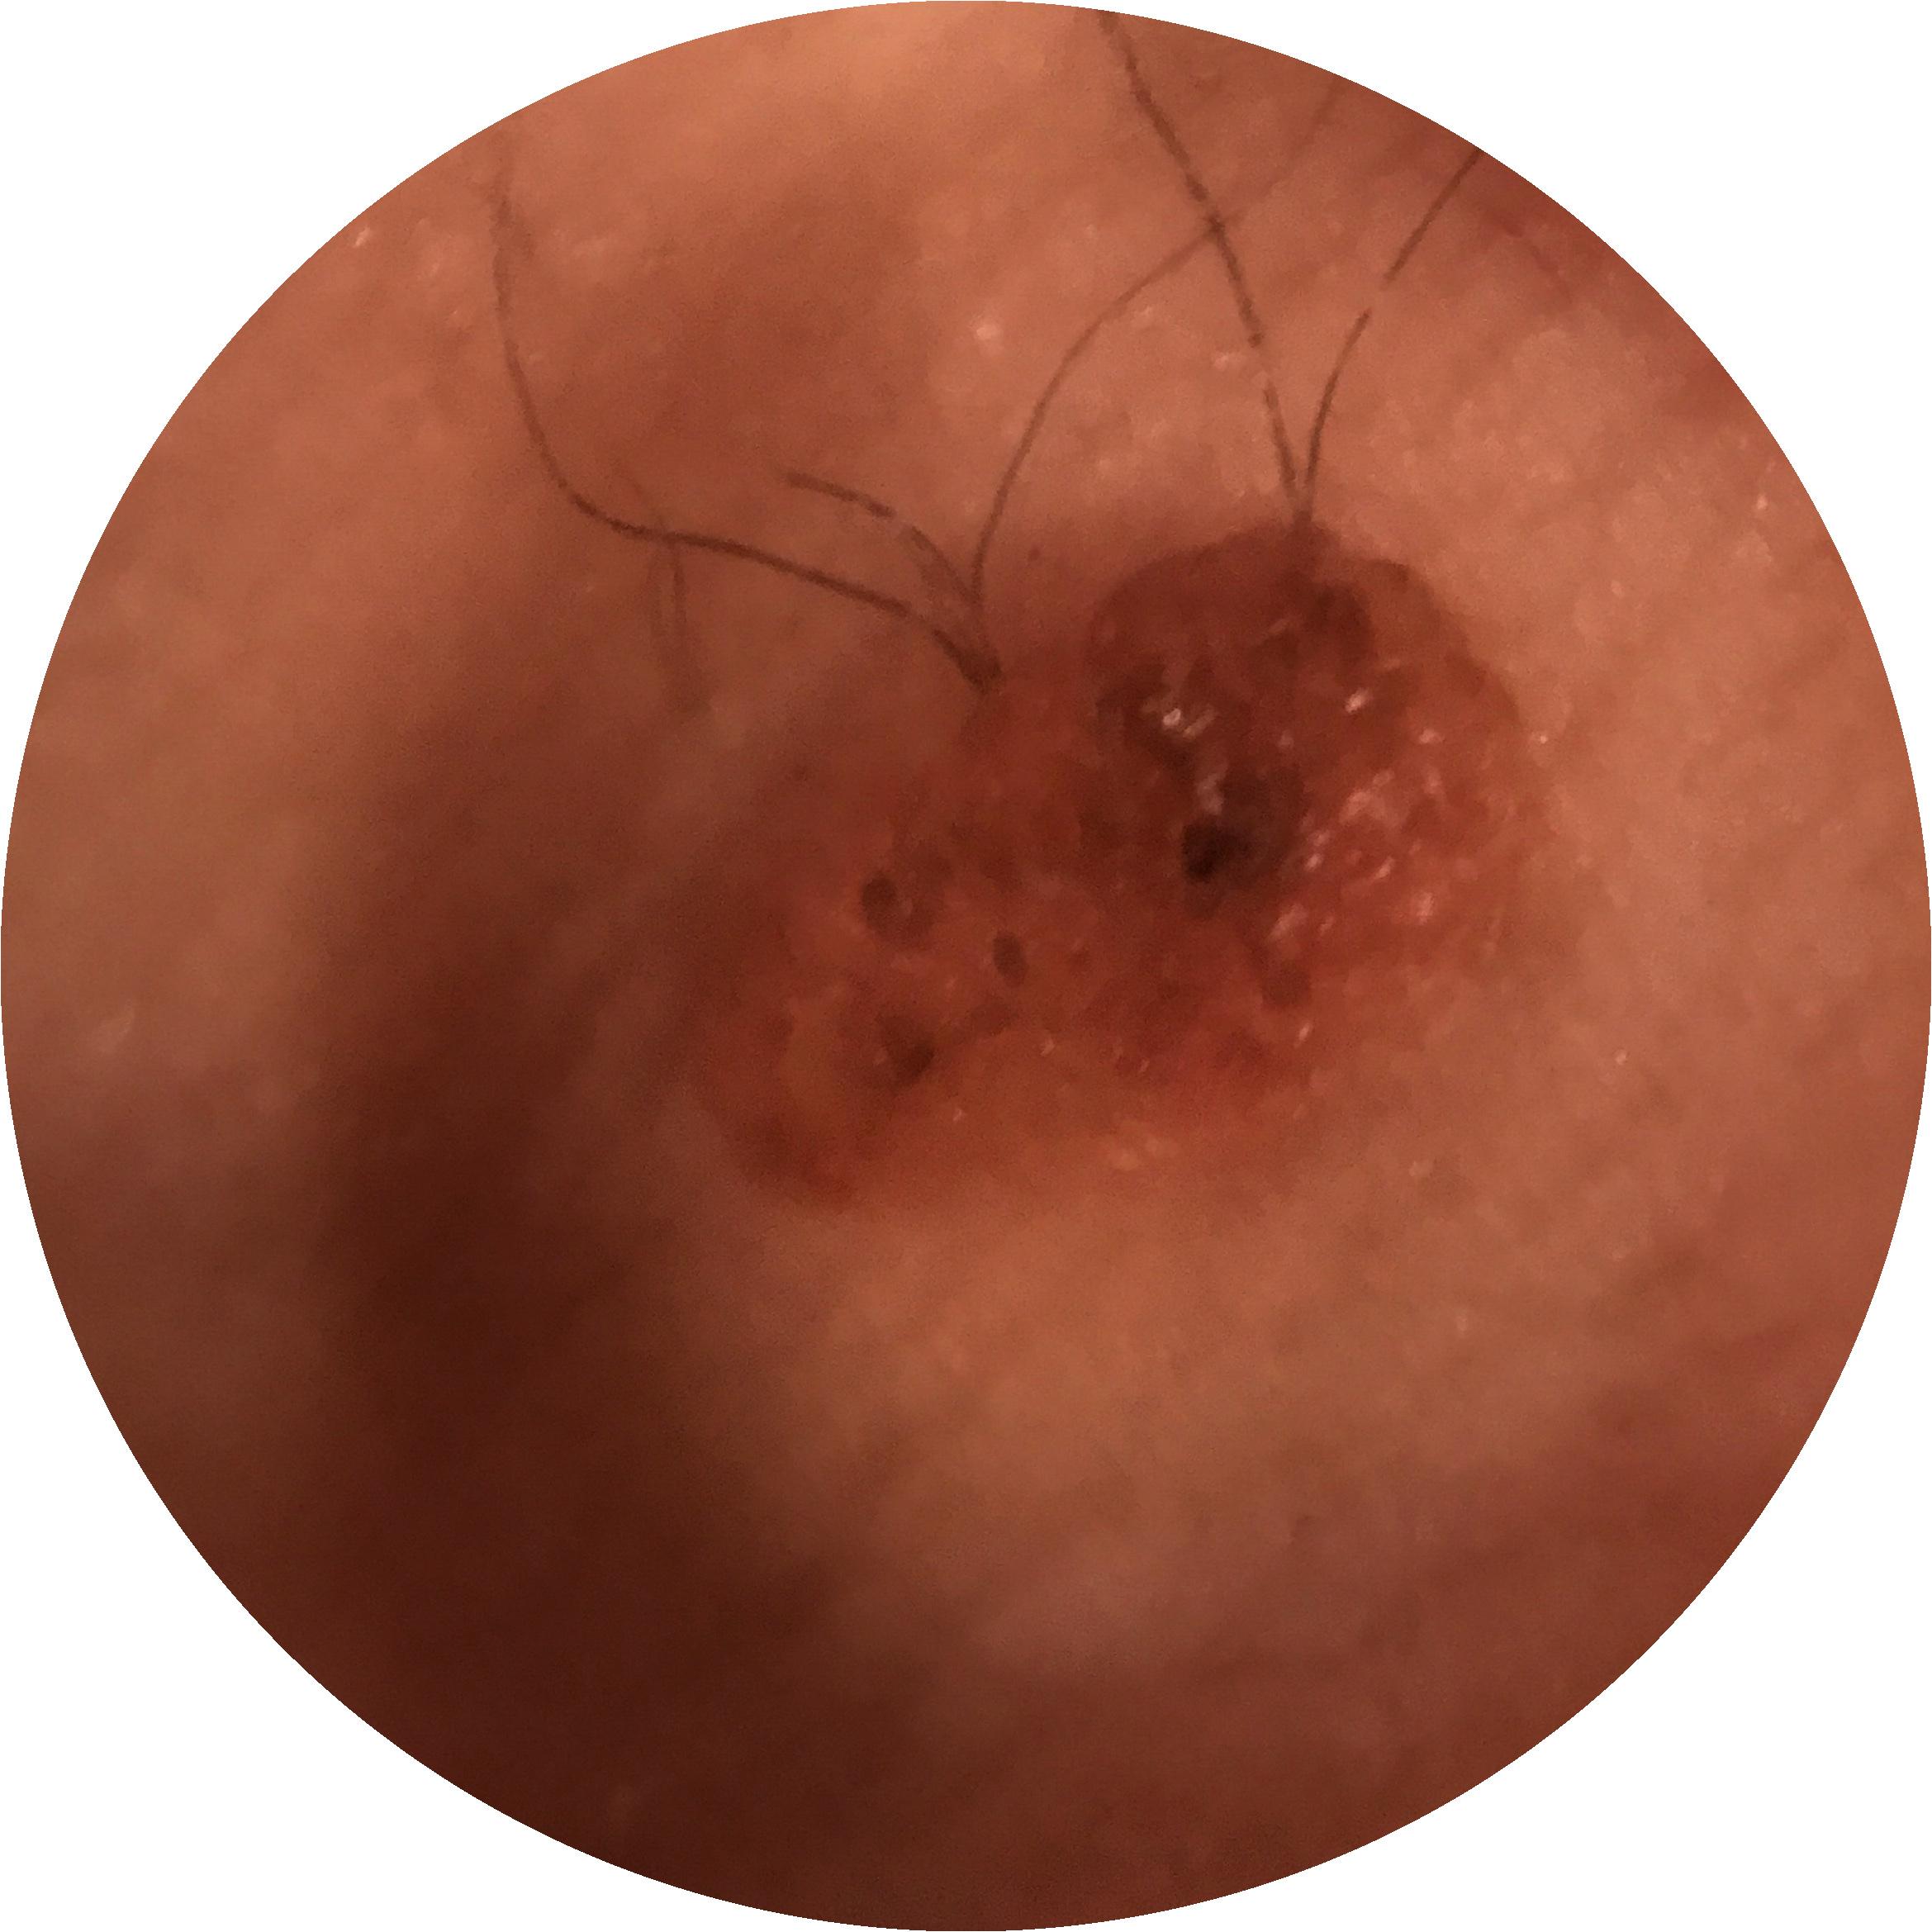

ISIC_4902807

710 x 710

Clinical

Field Value

acquisition_day 207

age_approx 45

anatom_site_1 Upper extremity

anatom_site_general upper extremity

diagnosis_1 Benign

diagnosis_confirm_type single image expert consensus

fitzpatrick_skin_type I

image_type dermoscopic

personal_hx_mm True

sex female